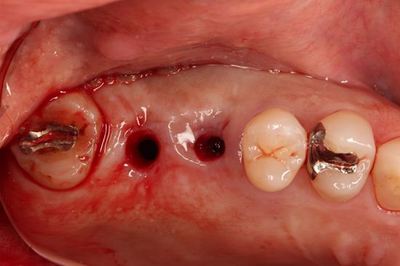

左上臼歯部のミラー像です。

![]()

口腔内での適合を確認します。